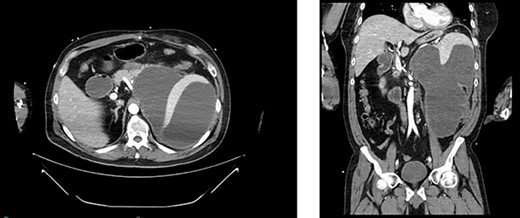

(A) Immunostaining for CD31 (100×) strongly marked lesional cells, supporting the diagnosis of AS and excluding sarcomatoid RCC; (B) routine H&E-stained section (100×) demonstrating an infiltrative pattern sarcomatoid tumor with variable cellularity and characteristic slit-like spaces, including red blood cells, characteristic of AS; benign adrenal tissue is visible on the left; (C) routine H&E-stained section (100×x) demonstrating angiosarcomatoid pattern with benign glomeruli.

The resected tissue was stained with routine hematoxylin–eosin (H&E) and was immunostained with CD31 (Fig. 2a–c). Histological examination of the resected left kidney and adrenal gland revealed high-grade, multifocal AS with sarcomatoid and rhabdoid features and extensive tumor necrosis. The margins of the ureter, renal vasculature and soft tissue were negative for malignancy. The sarcoma involved the tissue surrounding the adrenal gland but abutted the adrenal capsule. The tumor was staged as Stage IV, Grade 3 and T3N1M0. Examination of the resected periaortic lymph node revealed AS with involvement of one lymph node and adjacent perinodal soft tissue.